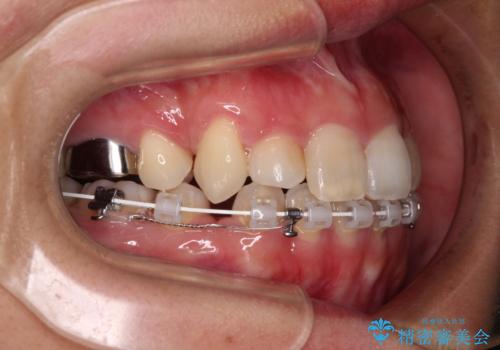

目立たない装置を希望されたので、上顎が裏側装置のハーフリンガルを選択し、上下左右の小臼歯(計4歯)を抜歯して矯正治療を行うこととしました。

補助装置を併用することで、八重歯を速やかに改善し、治療期間の短縮を図ることとしました。

補助装置を用いて抜歯したスペースを速やかに閉じたことで、短期間での治療となりました。